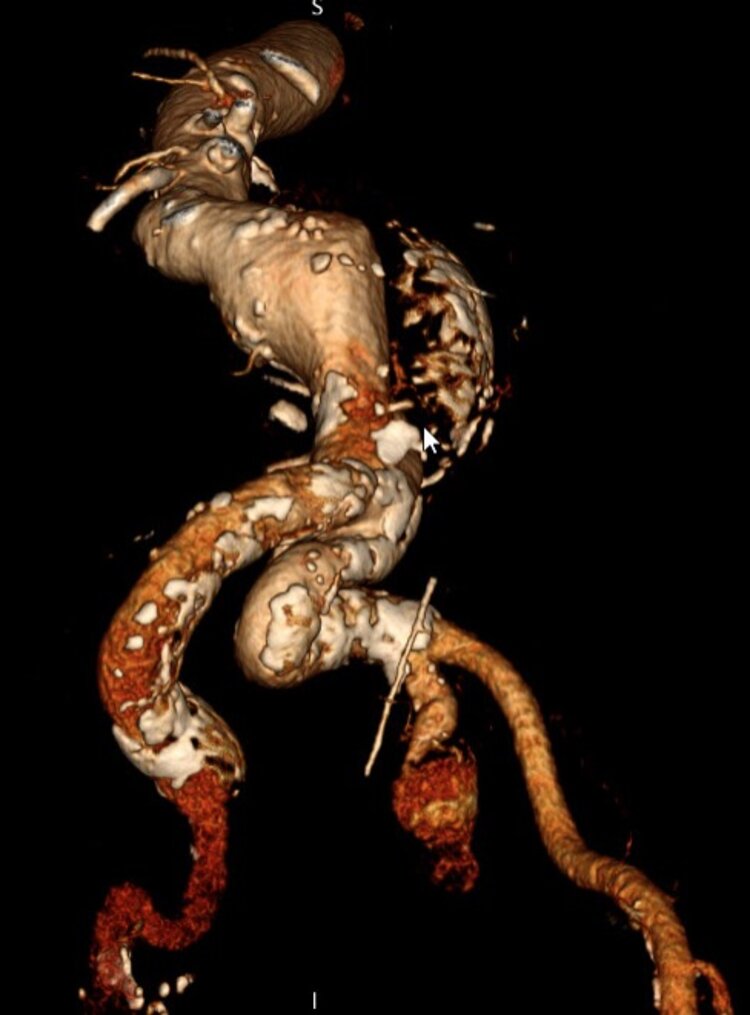

Ab einer bestimmten Grösse bzw. dem Vorliegen von Beschwerden ist die eine Sanierung notwendig. Diese kann entweder minimalinvasiv (endovaskulär) durch spezielle Stents (Gefässstützen) oder offen operativ mit Rekonstruktion des Gefässes oder Anlage eines Bypasses erfolgen.

Die Diagnosestellung erfolgt in der Regel per Ultraschall, ist oftmals aber auch ein Zufallsbefund, so dass die Erstdiagnose auch in einem CT oder Kernspin erfolgen kann (Abbildung 1 a–c). Meistens jedoch wird zuerst mittels Ultraschall geschaut und ggf. im Anschluss eine CT- oder Kernspinuntersuchung durchgeführt um die genaue Grösse und Ausdehnung festzustellen.